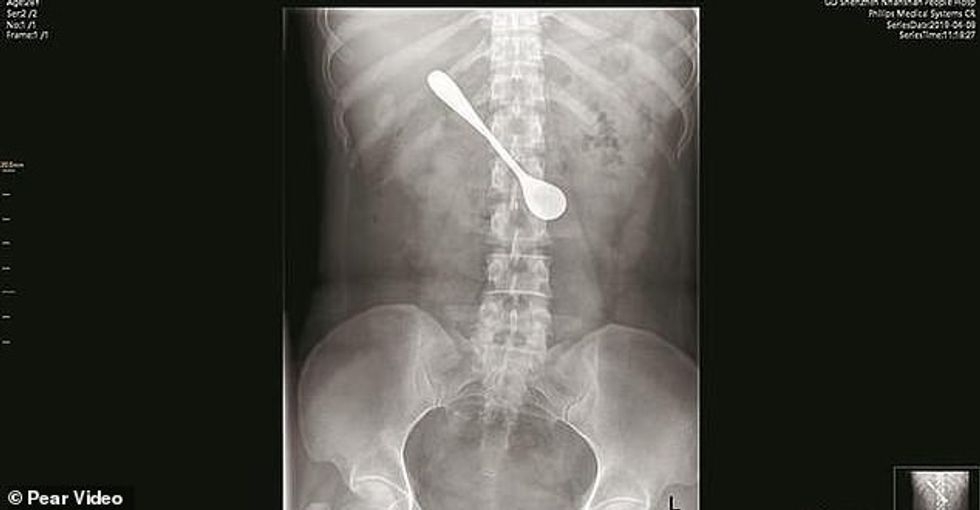

Një grua në Kinë u detyrua të bënte ndërhyrje kirurgjikale pasi hëngri një lugë metali aksidentalisht. Ajo po përpiqej të nxirrte në halë peshku që i kishte mbetur në fyt.

Gruaja e njohur si Lili përpiu edhe lugën 13 centimetra në përpjekje për të nxjerrë halën. Ajo qëndroi ashtu për 4 ditë pasi nuk ndjente dhimbje, por familjarët insistuan që të bënte kontroll.

Pas endoskopisë u zbulua luga që kishte mbetur në trup, në afërsi të lukthit.

Mjekët ia dolën që ta nxirrnin metalin me një ndërhyrje kirurgjikale që zgjati 10 minuta. Ata i kursyen gruas disa probleme serioze që do ti shfaqeshin në të ardhmen. /oranews/